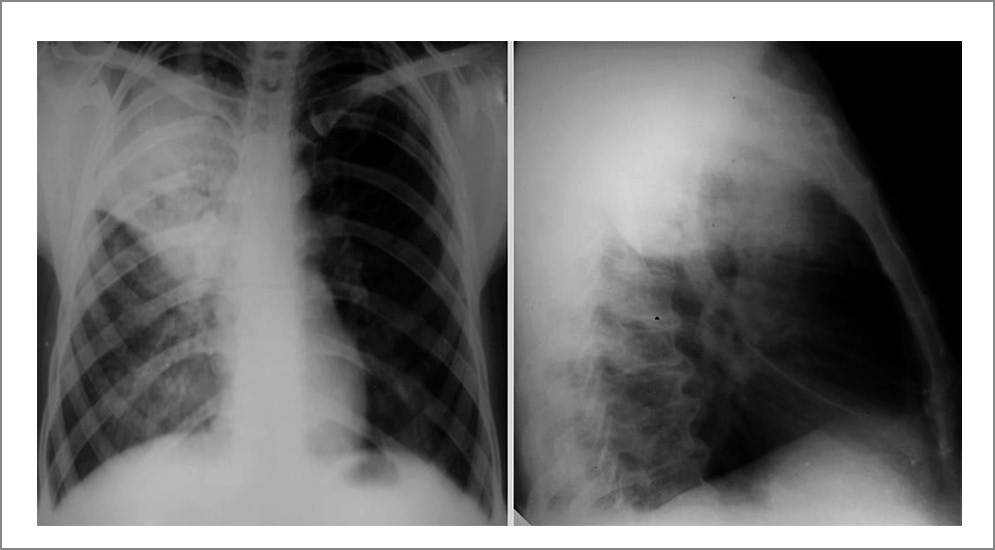

Для COVID-19 и вируса гриппа типичными проявлениями при рентгенографии ОГК являются многочисленные уплотнения легочной ткани различной формы, интенсивности и протяженности (чаще панлобарное периферическое или базальное расположение), диффузное альвеолярное повреждение легких (симптом «белых легких»). Чаще всего поражение носит двусторонний характер, а площадь вовлечения сегментов легких коррелирует с тяжестью течения болезни (рис. 2).

Рис. 2. Типичные изменения легочной ткани при COVID-19: панлобарные многочисленные уплотнения легочной ткани. Из личного архива авторов Т.А. Гутырчик, А.Б. Малахова.